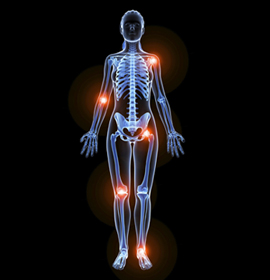

Las articulaciones experimentan un desgaste producido por el tiempo y también por lesiones que perjudican a la estructura articular. Los diferentes tipos de articulaciones sufren patologías que provocan molestias y en ocasiones trastornos graves a los pacientes.

Cuando el cartílago se rompe y se desgasta, los huesos se rozan. Esto a menudo provoca dolor, hinchazón y rigidez de OA. A medida que la OA empeora, se pueden formar espolones óseos o hueso adicional alrededor de la articulación.